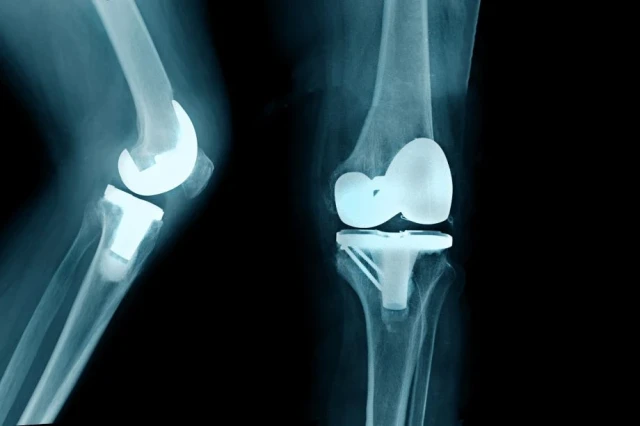

The Pros & Cons of Bilateral Knee Replacement

A bilateral knee replacement is when both knees are replaced during the same surgical procedure. Learn which patients are strong candidates for this procedure and the challenges during and after surgery.